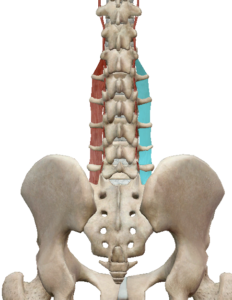

(2) 요외측횡돌기간근

요외측횡돌기간근은 요추에 있는 횡돌기간근입니다.

횡돌기 사이사이에 존재하며 척추 측굴시 안정성과 측굴을 만들어냅니다.

(3) 요방형근

요방형근은 12번 늑골, 요추 횡돌기에서 장골능으로 연결되어 있습니다.

양측성 수축 시 골반의 전방경사를 발생시킵니다.

편측성 수축 시 한 쪽 골반의 거상 또는 척추의 측굴을 발생 시킬 수 있습니다.